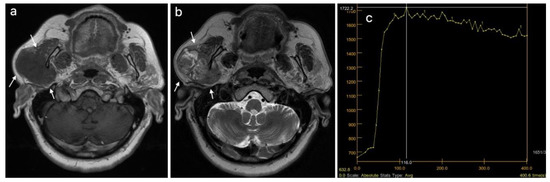

| MRI, T1 weighted image, n (%) | 0.024 | ||

| Hyperintense signal | 1 (5.26) | 7 (24.14) | |

| Mixt signal intensity | 3 (15.79) | 11 (37.93) | |

| Hypointense signal | 15 (78.95) | 11 (37.93) | |

| MRI, T2 weighted image, n (%) | <0.001 | ||

| Hyperintense signal | 12 (63.16) | 3 (10.34) | |

| Mixed signal intensity | 6 (31.58) | 20 (68.97) | |

| Hypointense signal | 1 (5.26) | 6 (20.69) | |

| DCE MRI, TIC curve, n (%) | <0.001 | ||

| Type A | 14 (73.68) | 0 (0) | |

| Type A, C | 1 (5.26) | 0 (0) | |

| Type B | 3 (15.79) | 11 (37.93) | |

| Type C | 1 (5.26) | 18 (62.07) | |

| DCE MRI, TTP (ms), median (IQR) | 210 (166.15–228.9) | 88.5 (82–101.9) | <0.001 |

| DWI MRI, ADC × 10−3 mm2/s, median (IQR) | 1.5 (1.25–2.1) | 0.86 (0.73–1) | <0.001 |